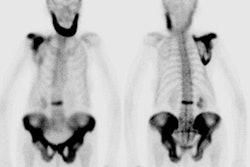

|

"Superscan" in patient with prostate cancer: A "Superscan" occurs in a patient with widespread osteoblastic bone metastatses. There is diffuse, intense skeletal uptake of the tracer with absent renal and background activity. |